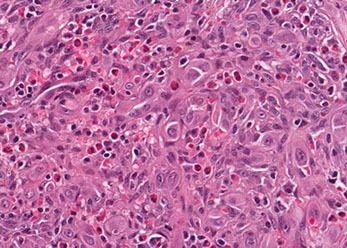

C, Epithelioid angiosarcoma demonstrates focal vasoformative features. The tumor is diffusely positive for CD31 (D) and Friend leukemia integration 1 transcription factor (FLI1) (E), with a variable CD34 expression (F) (hematoxylin-eosin; original magnification x20 [D through F]).

Angiosarcoma

Rare tumor in adults, (<1% of sarcomas), ~7th decade (very rare in kiddos) derived from endothelial cells of blood vessels that can occur in multiple sites depending on type of risk factor exposure

- skin>> breast > ST > solid organs > bone

- well differentiated (hemangiosarcoma) to anaplastic tumor that can look like melanoma or carcinoma

- risk factors: chronic lymphedema, PVC, radiation (esp breast), sun exposure, Thorotrast

Micro: atypical vascular spaced lined by endothelial cells c atypia and multilayering that involves subQ and has RBCs in intracytoplasmic lumina in more solid areas

- lots of mits and necrosis

IHC: (+) Factor 8 related peptide, CD31, Ki-67, FLI-1, thrombomodulin, CD34, c-kit, VEGFR-3, ERG, INI-1 (is lost in epithelioid sarcoma)